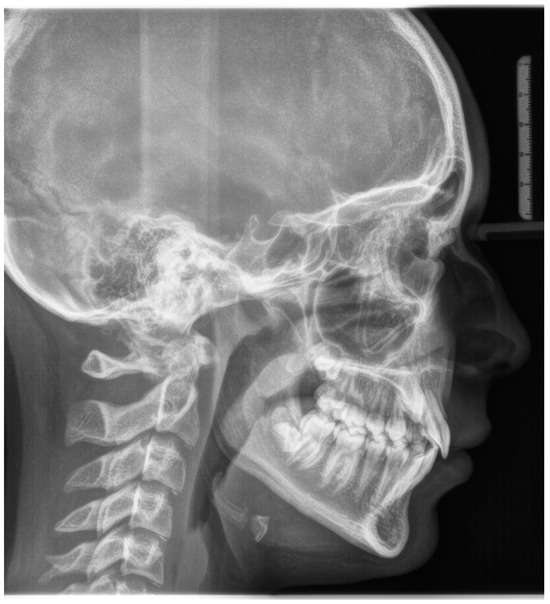

A 12-year-old girl with the second skeletal class (ANB 5), a high angle (FMA 27), and a facial index of 0.67 was selected. Soft tissue analysis showed a convex profile with a Z angle equal to 57 and an FMIA angle close to 55. The IMPA angle was 98. The analysis of the dental cast revealed a spee curve of 3.5 mm (Table 1). The occlusion presented a first molar class to the left, and a light second class to the right with 1 mm crowding in the lower jaw. The overjet was 0. The upper canines were impacted (Figure 1, Figure 2 and Figure 3). The patient’s chief complaint was altered aesthetic perception due to reduced dimensions of the deciduous canines. The treatment objectives were to retrieve space for upper canines’ eruption, level the spee curve, upright the lower incisors, and reduce the impact of the convex profile through occlusal vertical control to facilitate counterclockwise mandibular rotation.

Figure 3. Initial lateral cephalogram.